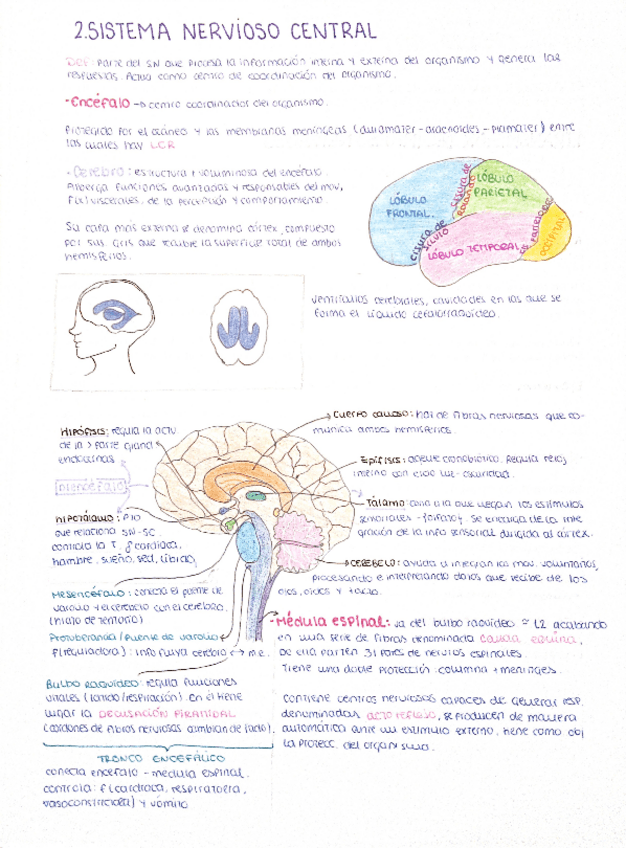

He publicado nuevos apuntes de Fisiopatología general: sistema-nervioso.pdf

He publicado nuevos apuntes de Fisiopatología general: Tema-7-Fsiopatologia-neurologica.pdf